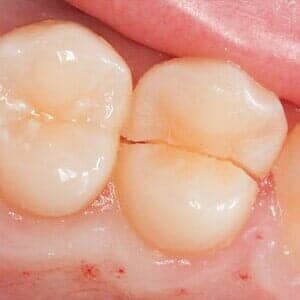

TMJ-CLENCHING OR GRINDING

Some people are quite aggressive in clenching their teeth while they sleep and others actually grind them and wear them down. These activities are often associated with jaw joint pain (TMJ) and headaches or migraines. It can also lead to cracked or broken teeth as well as your teeth becoming loose or cold sensitivity. Most commonly this is treated with a variety of mouth guards or bite adjustments. In some cases, injections are done in the chewing muscles which is used to reduce pain and hyper-activity.